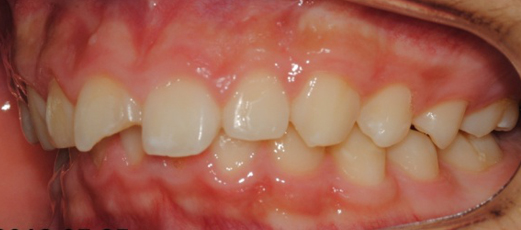

°ú°³±³ÇÕ°ú ¹«ÅÎ,ÅΰüÀýÀ» ÁÖ¼Ò·Î ³»¿øÇÏ¿© ÅμºÀå ¾ÇÁ¤ÇüÀåÄ¡¸¦ ÀÌ¿ëÇÏ¿© Ä¡·áÁßÀΠȯÀÚ·Î Ä¡·á½ÃÀÛ½ÃÁ¡ ±âÁØÀ¸·Î ÇöÀç ۰¡ ¾à 8cmÁ¤µµ ¼ºÀåÇÏ¿´½À´Ï´Ù. (Âü°í·Î 2³âÂ÷ ¿©µ¿»ý°ú ۰¡ 7-9cmŰ Â÷À̳²)